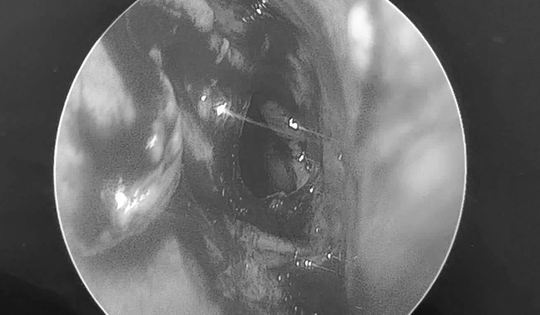

Cháu bé đau tai dữ dội, bác sĩ sốc ngang phát hiện bí mật "đáng sợ" bên trong